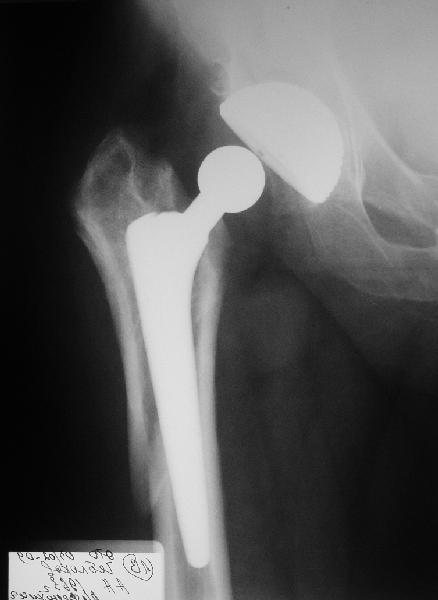

Мужчине 1963 г.р. в октябре прошлого года в Кургане сделано эндопротезирование правого тазобедренного сустава (последствия перелома шейки бедра) бесцементным протезом Cerafit.

Госпиталирован по месту жительства (МСЧ г. Новоуральск). Уложен на скелетное вытяжение. На снимках от 3 февраля видно миграцию ножки в дистальном направлении, она явно нестабильна. В нашей больнице вряд ли что-то удастся сделать. Сопутствующих заболеваний нет. Хотелось бы получить совет по тактике. Если нужно ревизионное протезирование, куда лучше пациента направить? Спасибо.

У пациента перипротезный перелом бедра тип 2Б по ванкуверской классификации.